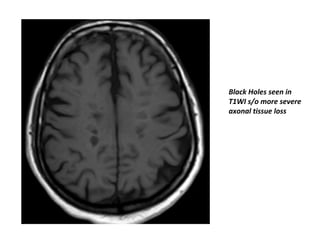

“Black Holes”

• In some patients many of the typical T2

hyperintense signal change has a T1

hypointense imaging characteristic , the so-

called ‘T1 black holes’.

• This phenomenon can be seen in two instances with

largely independent mechanisms

– Acute T1 black holes are seen in an early transient stage in

lesion formation. Cellular infiltration in emerging lesions

and associated ‘focal edema’ are thought to be the

pathological correlate. These often resolve.

– However, approximately 30% of T1 ‘black holes’ will

persist, becoming a lifelong present feature. When

persistent, these are thought to represent more severe

tissue loss with areas of axonal injury, the degree of

hypointensity correlated best with axonal density . The

most hypointense black holes can have little to no

remaining neuronal tissue . However, in most cases the

signal intensity is higher than CSF in these areas, indicating

persistence of (some) CNS tissue.

Black Holes seen in

T1WI s/o more severe

axonal tissue loss